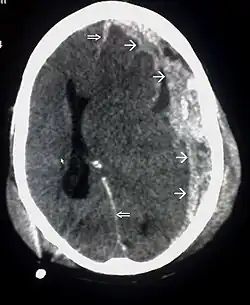

CT scan showing spread of the subdural hematoma (single arrows), midline shift (double arrows)

Systems also exist to classify TBI by its pathological features.[20] Lesions can be extra-axial, (occurring within the skull but outside of the brain) or intra-axial (occurring within the brain tissue).[24] Damage from TBI can be focal or diffuse, confined to specific areas or distributed in a more general manner, respectively;[25] however, it is common for both types of injury to exist in a given case.[25]

Hematomas, also focal lesions, are collections of blood in or around the brain that can result from hemorrhage.[11] Intracerebral hemorrhage, with bleeding in the brain tissue itself, is an intra-axial lesion. Extra-axial lesions include epidural hematoma, subdural hematoma, subarachnoid hemorrhage, and intraventricular hemorrhage.[38] Epidural hematoma involves bleeding into the area between the skull and the dura mater, the outermost of the three membranes surrounding the brain.[11] In subdural hematoma, bleeding occurs between the dura and the arachnoid mater.[23] Subarachnoid hemorrhage involves bleeding into the space between the arachnoid membrane and the pia mater.[23] Intraventricular hemorrhage occurs when there is bleeding in the ventricles.[38]